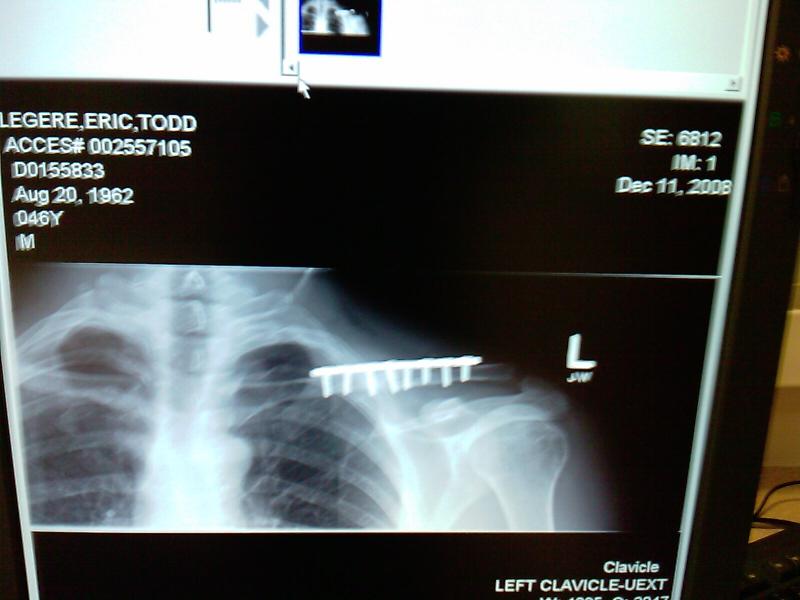

Wow, Legtod, Looks like you got the clavicle surgery I probably should have gotten. The X-ray below is from five months after the break. Essentially it’s the “after” shot. Bone filled in around the break to connect the pieces, but it’ll never be the same again…

(Trivia for legtod2: You have my wife’s birth date and my birth year. Also, the people you listed as your inspiration in life have the same last names as the two “friendly rival” families that hosted the first several USA National Unicycle Meets. The Pontiac Unicycle Club (Crandall), 1973 and 75, and the Paul Fox Unicycle Club (Ohio), 1974, 76, 77.)